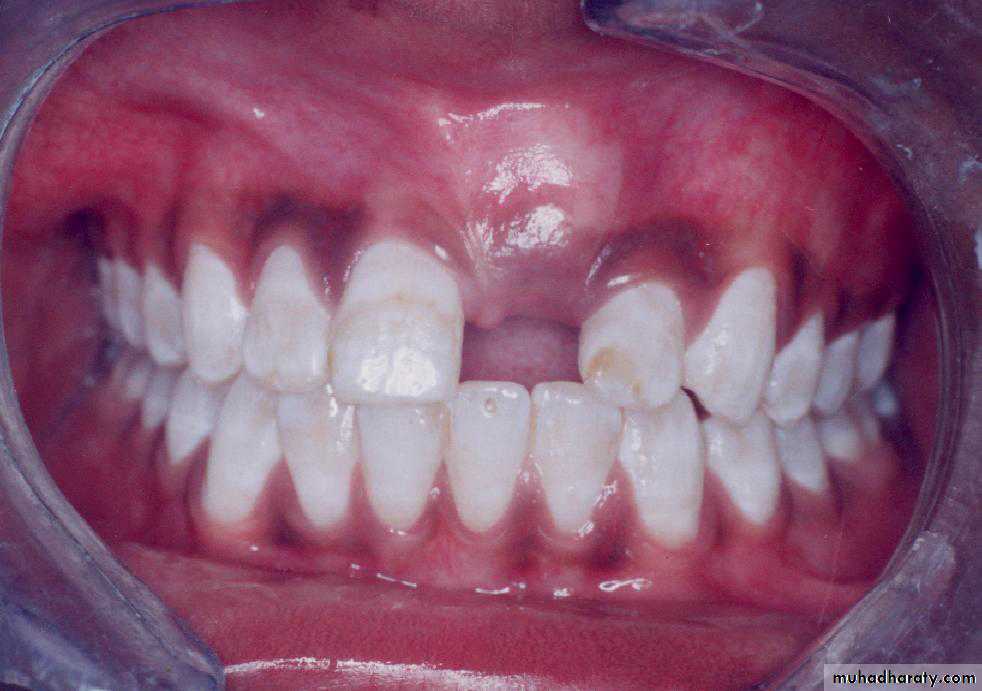

Surgical exposure :the path of eruption is not obstructed

Surgical exposure with orthodontic traction: the path of eruption is obstructed